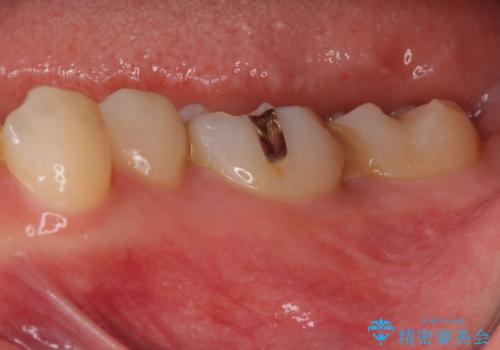

処置開始前から神経組織を部分的に除去する可能性が高いことが分かっていたため、ラバーダムなどの環境を整え、無菌的環境下にて処置を進めて行きました。

虫歯は深くまで進行しており、歯冠部後方の神経から出血が認められました。炎症を起こしている神経を除去したところ出血が治まったので、生体親和性の非常に高いセメントにて充填し、仮封をし、その日のうちに仮歯を装着しました。

後日状態を確認したところ、残された神経に異常がなかったため、フルジルコニアクラウンにて補綴治療を行いました。